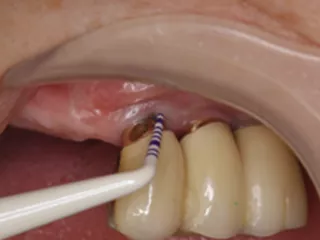

CASE No.4 大月 基弘 先生(大阪府大阪市開業)

Labrida 施 術 前

施 術 前 (レントゲン写真)

Labrida 施 術 後(2週後 )

PPD7㎜からPPD3㎜、

BOP(ー)に変化、炎症消失